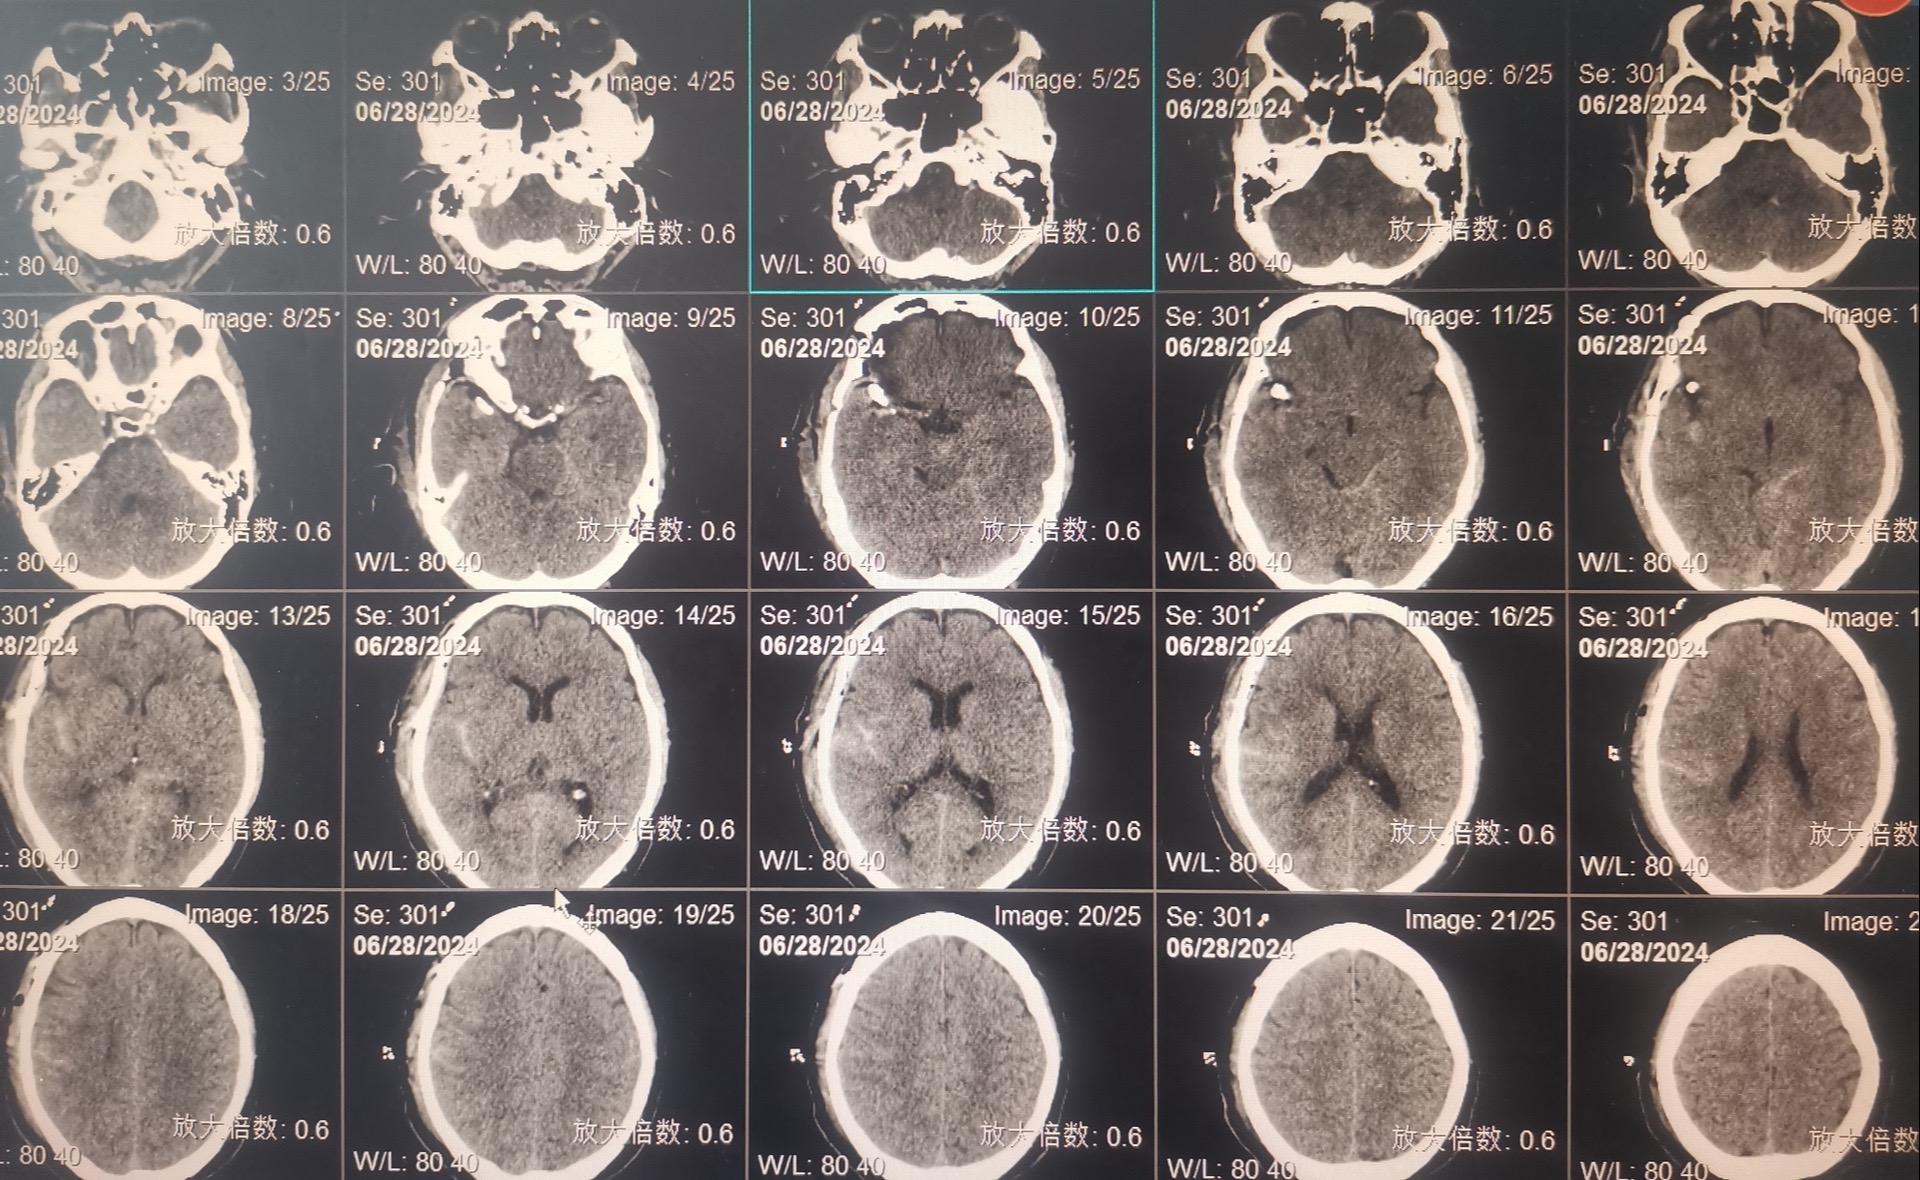

发现未破裂的脑动脉瘤就要作手术吗?慎重!40岁以上的人群中作CTA或者MRA体检筛查脑动脉瘤,发现率是7%!这是未破裂动脉瘤。 未破裂脑动脉瘤的治疗要慎重!要达到国家指南治疗标准才有治疗指征,有治疗指征也不是说必须作手术。 59岁男性,行脑部磁共振检查时发现一个脑动脉瘤,其大小约10x8毫米,位于右侧大脑中动脉,见图。 这个病人从来没有脑部出血病史,这样的动脉瘤需要治疗吗? 这个大脑中动脉动脉瘤直径超过5毫米,根据中国的未破裂脑动脉瘤治疗指南,是